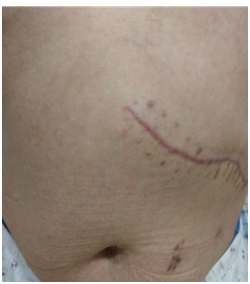

4、腹腔镜手术腹壁戳孔小(直径5—10mm不等),取代了传统腹壁大切口,避免了腹壁肌肉、血管和相应神经的损伤,而且切口隐蔽,愈合后瘢痕小,美容效果好。戳孔感染的发生率明显低于传统开刀手术。

图片

传统开腹手术

腹腔镜微创手术